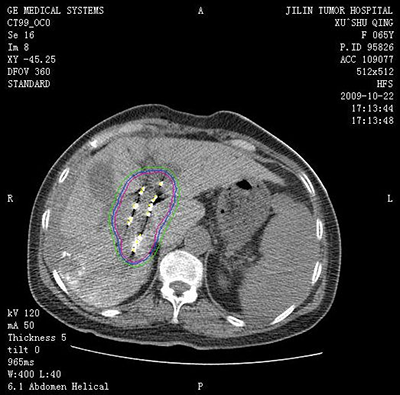

吉林省腫瘤醫(yī)院介入中心建筑面積2200平方米,開放床位35張。擁有UNIQ FD20C 血管造影機?,F(xiàn)有主任醫(yī)師1名,副主任醫(yī)師1名,主治醫(yī)師2名,醫(yī)師2名。(其中博士1名,碩士4名)??剖易?992年開展腫瘤介入微創(chuàng)的診療工作,30年以來,開展了肝癌、肺癌、肝轉(zhuǎn)移癌、肺轉(zhuǎn)移癌、膽管癌、消化道腫瘤、泌尿系統(tǒng)腫瘤、骨轉(zhuǎn)移瘤、盆腔腫瘤等各種良、惡性腫瘤的微創(chuàng)介入手術(shù)2萬余例(包括腫瘤動脈灌注化療栓塞術(shù)、微波消融術(shù)和125I放射粒子植入術(shù)(病種包括:肝癌、肝轉(zhuǎn)移癌、肺癌、肺轉(zhuǎn)移癌、骨轉(zhuǎn)移癌、腎上腺轉(zhuǎn)移癌等)、子宮肌瘤及肌腺癥栓塞術(shù)、經(jīng)皮穿刺骨水泥注射椎體成形術(shù)、食管、膽管狹窄支架置入術(shù)、各部位腫瘤急性出血的栓塞止血術(shù)、胃腸營養(yǎng)管、腸梗阻導(dǎo)管植入術(shù)等)。在國內(nèi)外首先提出低功率消融的治療理念,經(jīng)過1000余例臨床手術(shù)證實,療效確切,無并發(fā)癥,得到了國內(nèi)外同行的廣泛認(rèn)可,并在全國逐步推廣。2011年在國內(nèi)外率先開展三氧化二砷聯(lián)合局部微創(chuàng)介入治療中晚期肝癌的隨機對照研究,提出了早期全身干預(yù)與局部治療的序貫療法,取得了明顯的成績,經(jīng)過中位60個月隨訪期,治療組明顯優(yōu)于常規(guī)對照組,中晚期肝癌的5年生存期達到38.2%,達到了國際領(lǐng)先水平。在國內(nèi)率先開展了多項靶向藥及免疫治療聯(lián)合介入微創(chuàng)治療肝癌、肺癌等臨床研究,取得了較好的成績。在科研方面,共發(fā)表SCI及核心期刊論文100余篇;2019年度獲吉林省科技進步二等獎1項,吉林省科技進步三等獎1項,2014年獲長春市科技進步二等獎1項??剖覟榧质】拱﹨f(xié)會介入治療專業(yè)委員會主委單位,主辦國家級及省級學(xué)術(shù)會議10余次。

(肝癌的消融治療)(肺癌的消融治療)

(肝癌的粒子植入治療)(肺癌的粒子植入治療)

(骨惡性腫瘤的消融治療) (CT引導(dǎo)下骨水泥注射椎體成形術(shù)及粒子植入術(shù))